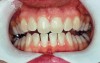

Figure 8  Prior to at-home whitening (left). Following approximately 10 days of at-home tray whitening (right).

Figure 8

Figure 9  Prior to at-home whitening (left). Following approximately 10 days of at-home tray whitening (right).

Figure 9